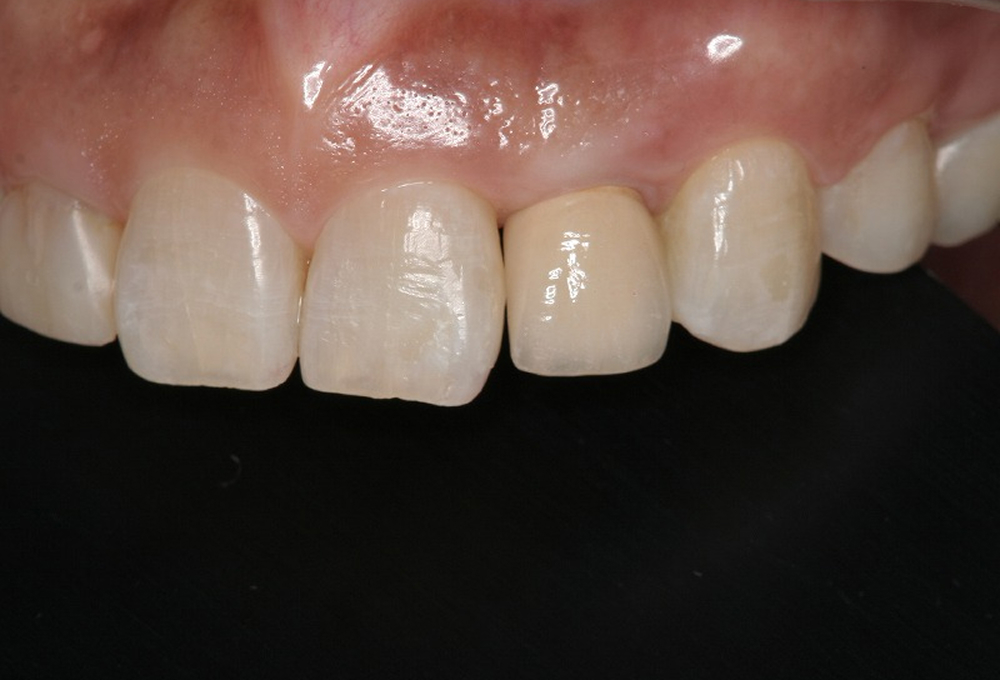

⑩術後 上顎